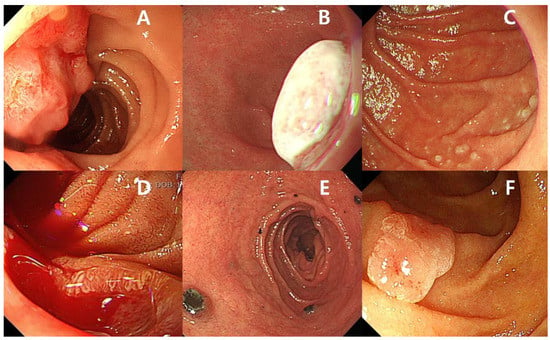

The small bowel is very long (6–7 m) and accounts for 75% of the length of the GI tract. Small bowel malignancies are rare, constituting only 1–3% of all GI malignancies [9]. Patients with small bowel tumors are usually asymptomatic or have only nonspecific symptoms, such as GI bleeding, anemia, abdominal pain, vomiting, and weight loss [10,11]. Previously, the diagnosis of small bowel malignancies was difficult because of the length of the small bowel and the limitations of the diagnostic tools [12]. The advent of CE and device-assisted enteroscopy (DAE) has revolutionized the diagnosis and management of small bowel diseases [2]. Small bowel malignancies are subdivided into primary and secondary based on origin. The most frequent types of primary small bowel malignancies are adenocarcinoma (Figure 1A), neuroendocrine tumors (Figure 1B), lymphoma (Figure 1C), and gastrointestinal stromal tumor (GIST) (Figure 1D) [12,13]. Secondary small bowel malignancies can develop by direct invasion or distant metastasis. Frequently, secondary small bowel malignancies originate from malignant melanoma (Figure 1E), as well as lung, breast, and colorectal cancers [14]. Known risk factors associated with primary small bowel cancers are Peutz–Jeghers syndrome (PJS), familial adenomatous polyposis (FAP), Lynch syndrome, Crohn’s disease, and celiac disease. Importantly, adenoma (Figure 1F) of the small bowel is a known precursor of small bowel adenocarcinoma [15,16,17]. Duodenal adenomas are also associated with FAP and Lynch syndrome [18]. The adenoma–carcinoma sequence in the small intestine was described, and the risk of progression to malignant neoplasm was similar to that in the colorectum [19]. The presence of duodenal adenomas, especially in young patients, suggests the possibility of hereditary polyposis syndrome, and indicates the need for colonoscopy to exclude colorectal neoplasms [19,20]. Some studies have reported a relationship between sporadic duodenal adenomas and colorectal adenomas [21,22,23]. An association between an increased risk of small bowel cancer and environmental factors, including alcohol consumption, smoking, red meat, and intake of sugary drinks, was reported, although the evidence is insufficient owing to the rarity of small bowel malignancies [17].

Figure 1.

(A) Adenocarcinoma of the small bowel. (B) Neuroendocrine tumor of the small bowel. (C) Follicular lymphoma of the small bowel. (D) Gastrointestinal stromal tumor of the small bowel with active bleeding. (E) Secondary small bowel malignancy originating from malignant melanoma. (F) Adenoma of the small bowel.